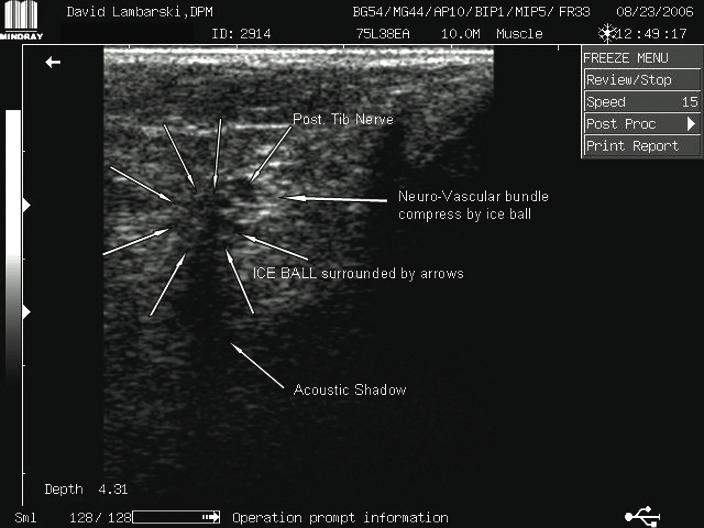

Combining Cryosurgery With Ultrasound: A Guide To Surgical Technique

The procedure involves palpating the posterior tibial artery just proximal to the level of the medial malleolus. We begin by providing anesthesia using a 1 cc syringe of 1% lidocaine with 100,000 dilution of epinephrine. One would inject this solution subcutaneously with a tuberculin syringe 2.5 cm superior to the medial malleolus directly over the posterior tibial artery. We proceed to prep the area in the usual sterile manner with Betadine® and protect the area with a Sound-Seal® thin film dressing (BioVisual Technologies), an FDA-approved protective film dressing for diagnostic ultrasound exams. Cover the area with the sterile dressing and mark the incision site using a sterile pen. A #11 sterile blade provides for a transverse 3 mm full-thickness skin incision. Take care not to violate any deeper structures. (In the aforementioned case study, we performed the procedure in the office under local anesthesia and without tourniquet assistance.) Using a blunt probe, gently penetrate the fascial tissue in the direction of the neurovascular bundle. Use the diagnostic ultrasound machine carefully to help create a tunnel for the cryosurgery probe. Insert the probe into the incision site while under the guidance of the diagnostic ultrasound scanner. We use the HydroStep® Standoff pad to help facilitate compliance over bony prominences such as the medial malleolus. The standoff pad also moves vital structures into specific ultrasound focus zones. The combination of compliance and the shifting of structures deeper into focus zones provides better image quality and resolution. Proceed to introduce the probe into the target area, namely the posterior tibial neurovascular bundle. Since the cryosurgery ice ball ranges in size of 3.5 to 10 mm, depending on environmental conditions, there is no need to dissect the nerve from its adjacent vein and artery. After inserting the probe with pressure directly on the neurovascular bundle, the freezing technique begins. This involves a three-minute freeze cycle, which causes an ice ball formation around the neurovascular bundle. One can directly visualize this process in real time using diagnostic ultrasound imaging. After the initial three-minute freeze, perform a 30-second thaw cycle followed by a second three-minute freeze cycle and 30-second thaw cycle. Generally, the ice ball will surround most of the neurovascular bundle as one can see on the diagnostic ultrasound screen. Once this cycle is completed, withdraw the probe. Dress the incision site with a sterile antibiotic ointment and a gauze compression dressing. No sutures are needed. Our general postoperative course involves no medications and no limitation of activity. The patient is able to shower the following day.